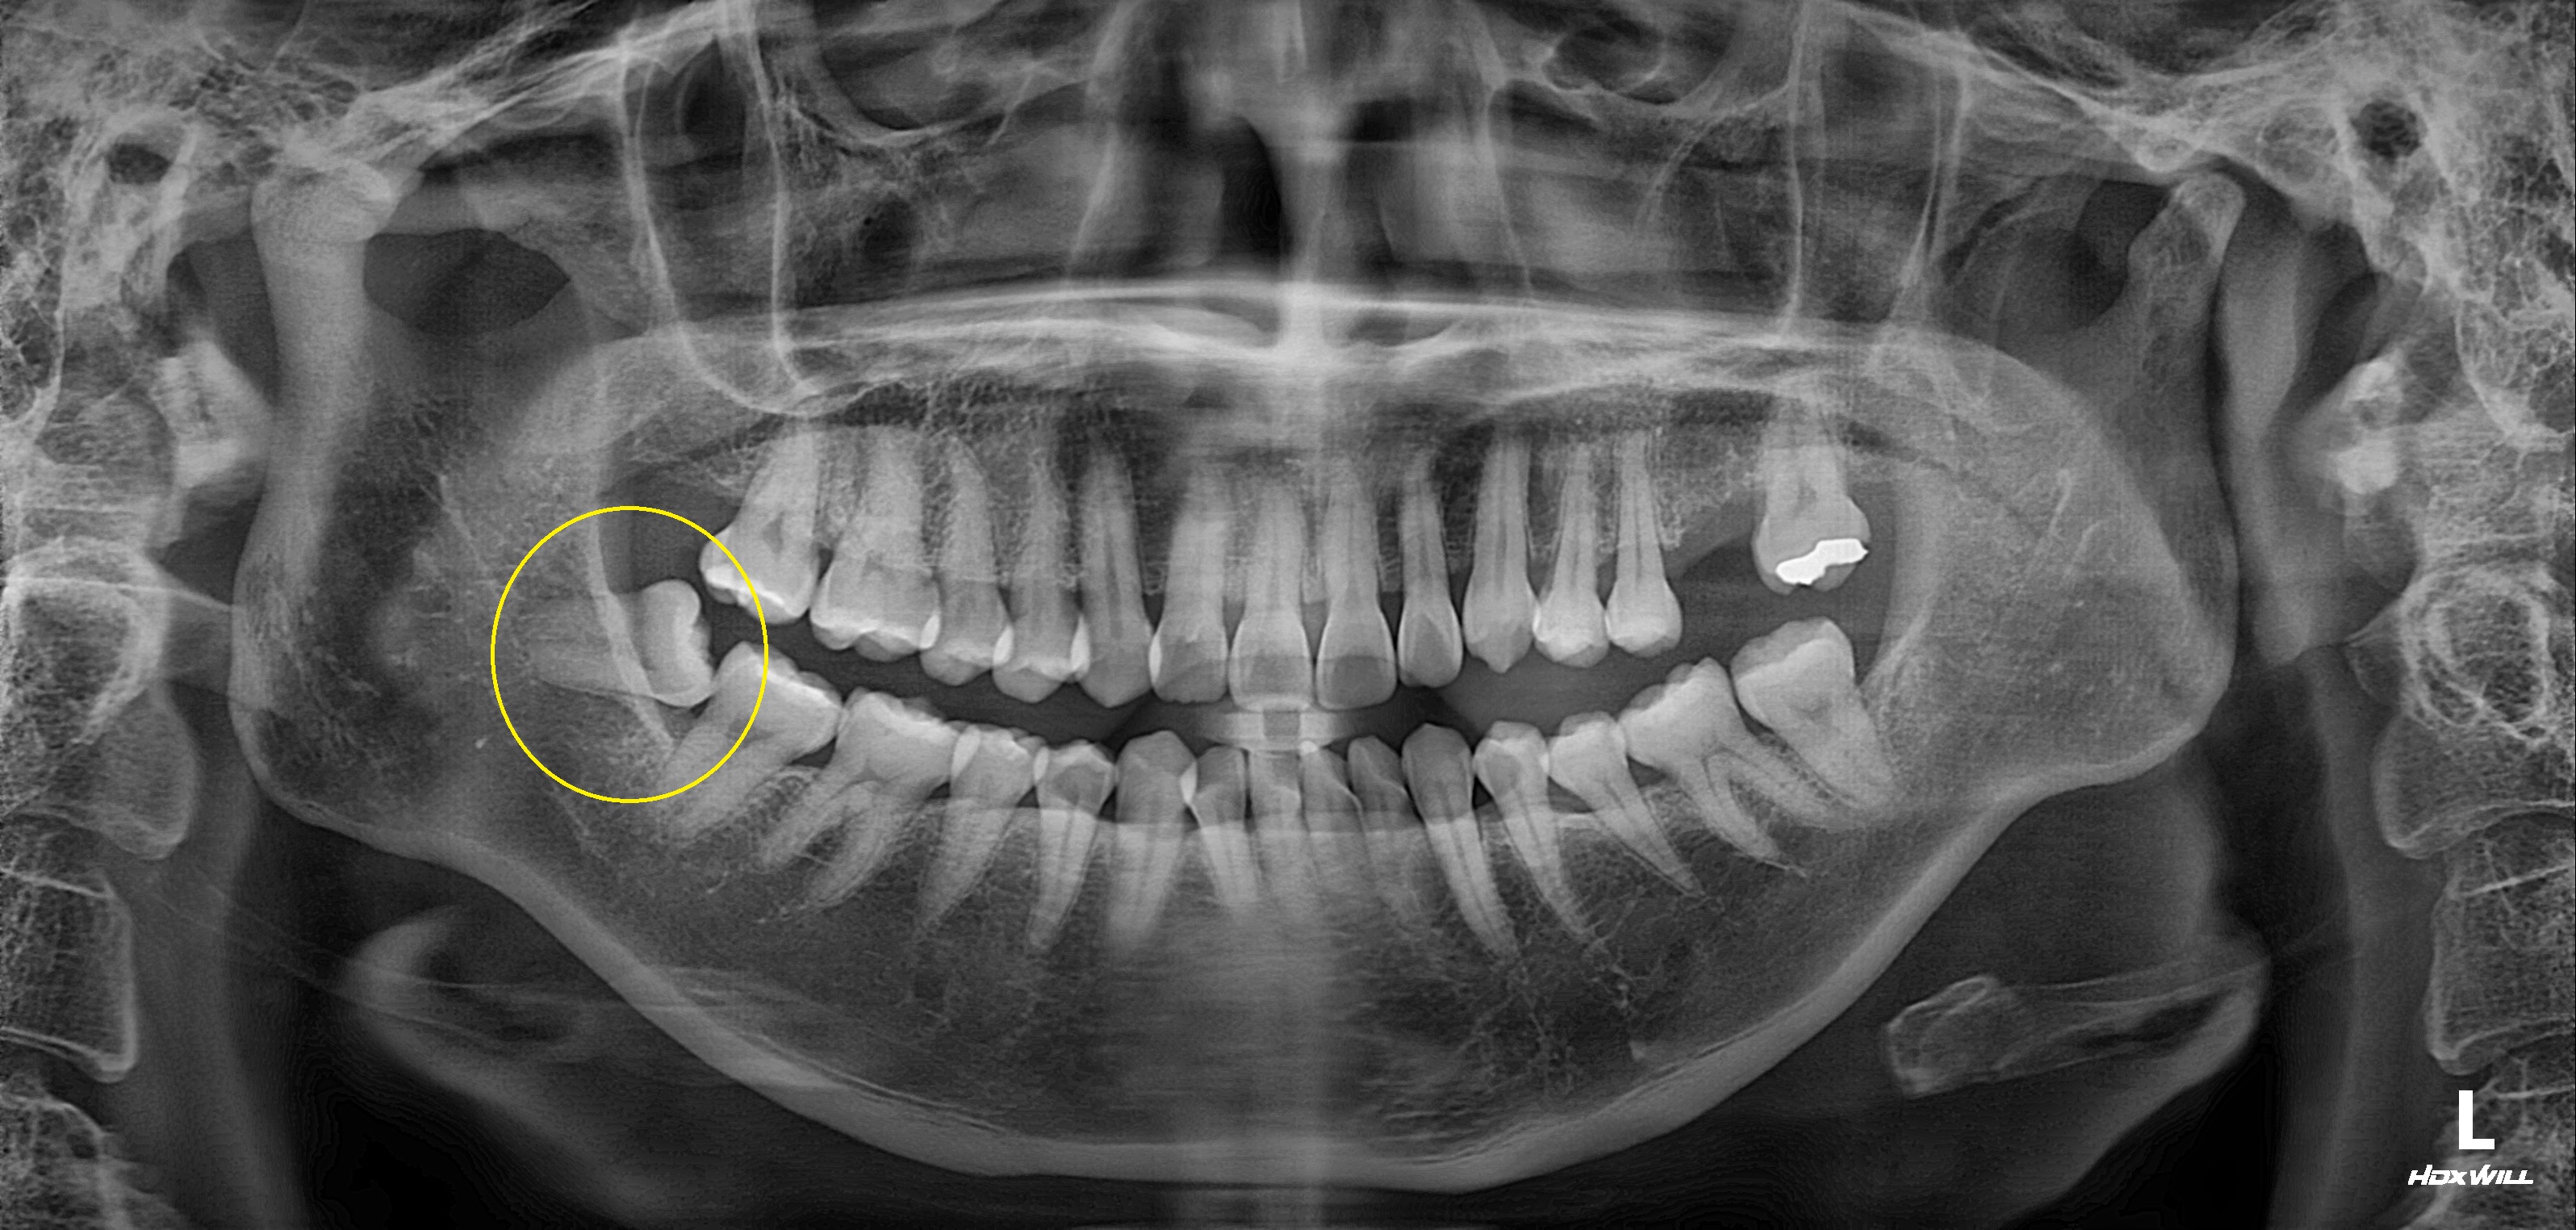

수술 전

수술 후

완전매복치발치사례

전후사진